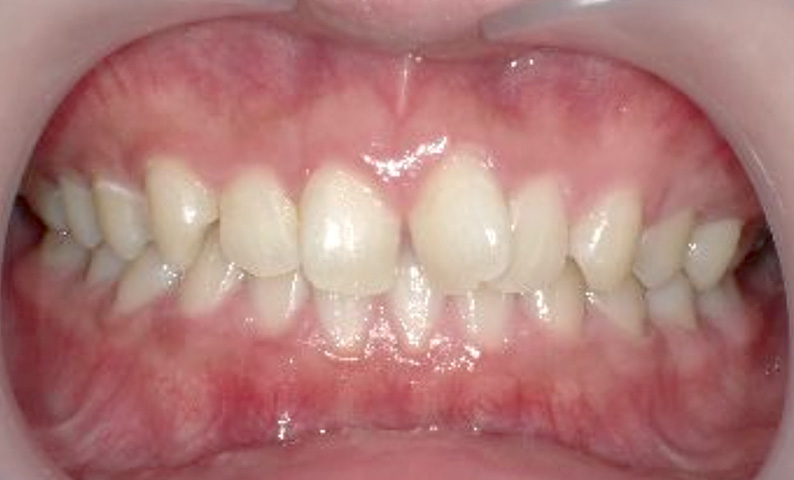

症例_005 上下顎の部分矯正

治療期間:11ヶ月金額:54万円+税女性前歯のガタガタ捻転歯

| Before | After |